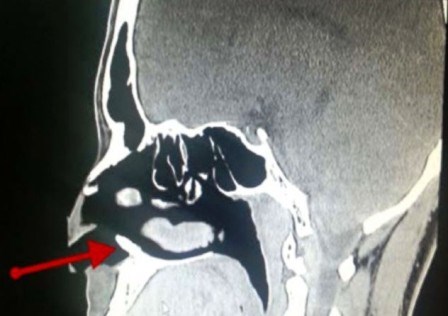

Vụ việc hi hữu xảy ra đối với một thanh niên ở A-rập Xê-út khi các bác sĩ phát hiện thấy một chiếc răng mọc bên trong lỗ mũi của anh này sau một thời gian dài chịu đựng những đợt chảy máu mũi bất thường.

Trong suốt ba năm liền, người thanh niên 22 tuổi (được giấu tên) phải chịu ít nhất một lần máu mũi chảy bất thường mỗi tháng. Sau khi đi đến bệnh viện khám, các bác sĩ bất ngờ phát hiện một chiếc răng mọc bên trong lỗ mũi của anh.

Báo cáo nghiên cứu do Tạp chí “Case Reports” được xuất bản ở Mỹ cho biết, đây là một chiếc răng khôn, thay vì mọc trong miệng thì nó lại nổi lên ở lỗ mũi gây nên hiện tượng chảy máu mũi.

Theo tờ Live Science, các bác sĩ ở bệnh viện quân y King Fahd tại Dhahran, Ả-rập Xê-út đã rất ngạc nhiên khi phát hiện thấy chiếc răng lại mọc trong lỗ mũi. Sau khi gây mê và tiến hành ca tiểu phẩu, chiếc răng trong lỗ mũi đã được loại bỏ thành công.

Bác sĩ John Hellstein, một trong những tác giả của bài nghiên cứu, giải thích rằng mặc dù hiếm gặp nhưng những chiếc răng khôn có thể phát triển gần răng cửa và trong một số trường hợp những chiếc răng khôn này có thể phát triển thẳng đứng lên phía mũi.